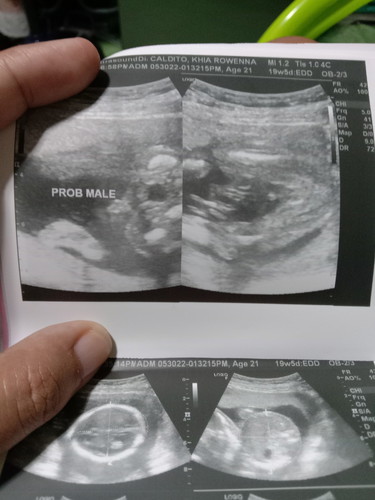

Kagabi sobrang sumakit ung balakang ko at ang tigas tigas ng tyan ko at sumasakit din halos di ako makatulog sa sakit naiiyak na ako at nung nasuka ako halos lahat ng kinain ko ng dinner nasuka ko at yun nga pagtapos ko magsuka gumaan na pakiramdam ko dinaan ko sa prayer kala ko naglelabor na ko sa sakit thanks God hindi pa Kasi mag 20 weeks pa lang c baby.đ #pregnancy20w#pregnancy